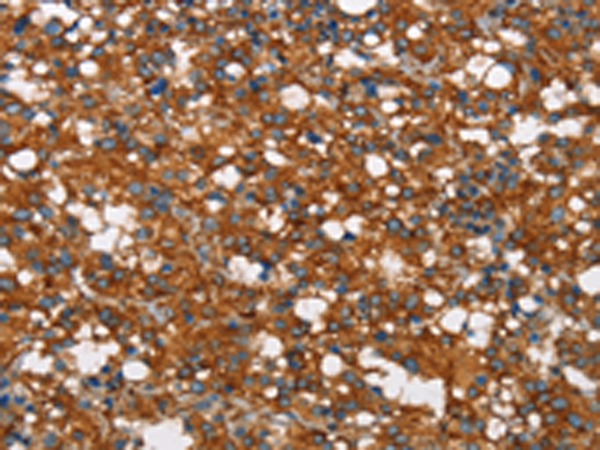

分类: 科研抗体货号: P11552别名: 5-HT3B应用: IHC反应种属: Human